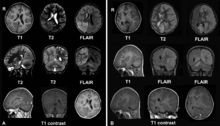

Brain MRI of an 8-year-old female with Rasmussen's encephalitis.

A. December 2008, the patient was presented with headache and epilepsia partialis continua. There are lesions with local brain swelling in the right parietal and occipital lobes and right cerebellar hemisphere.

B. April 2009, the same patient, now she is comatose with epilepsia partialis continua. There is progression of the encephalitis - the left cerebral hemisphere has been involved with severe brain swelling and shift of the midline structures.

The diagnosis may be made on the clinical features alone, along with tests to rule out other possible causes. An EEG will usually show the electrical features of epilepsy and slowing of brain activity in the affected hemisphere, and MRI brain scans will show gradual shrinkage of the affected hemisphere with signs of inflammation or scarring.[8]